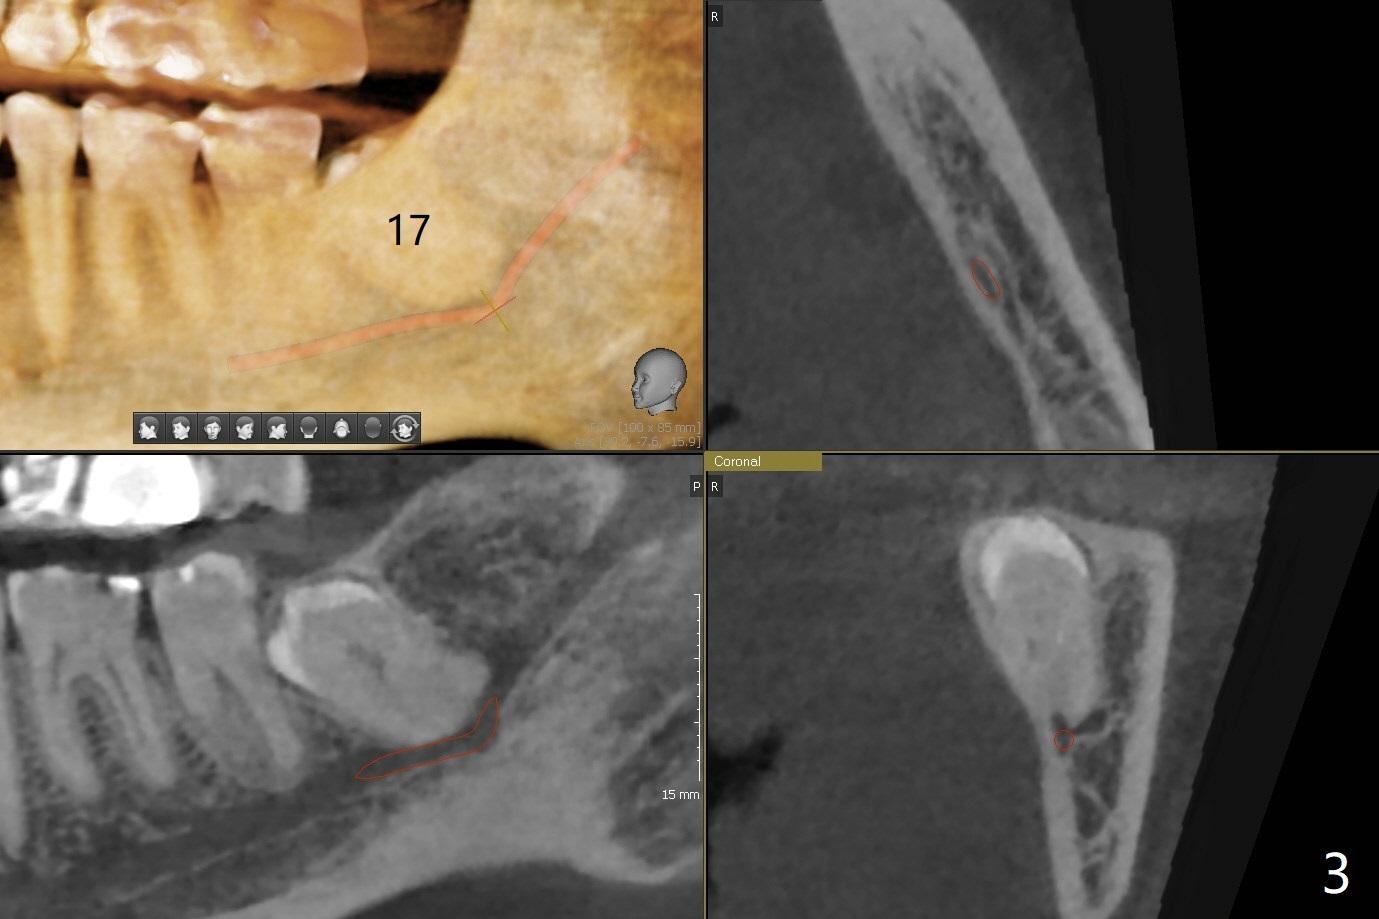

A 63-year-old woman wants to extract the tooth #18 with crack before termination of dental insurance (Fig.1). It is also possible to place an immediate implant in the septum (Fig.2). Socket shield is not needed because of the wide bone. If the implant is too close to the tooth #17, section the mesial portion of the latter (red dashed line), since removing the impacted tooth may risk injury to the Inferior Alveolar Canal (Fig.3,4). Draw one tube of blood for sticky bone.